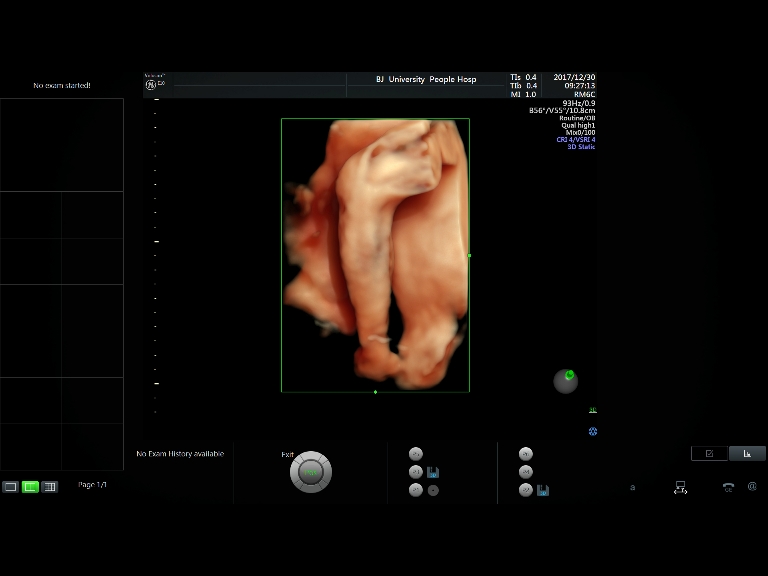

四维彩超图片

徐州四维彩超图片高清